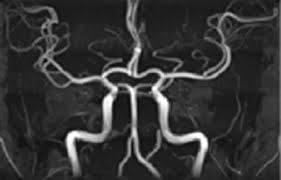

- MRA (자기공명혈관조영술): MRI 원리를 적용해 **혈관 내부 구조와 혈류 흐름**을 3D 영상으로 확인하는 검사입니다. 동맥류, 혈관 협착·폐쇄·혈전 등의 진단에 사용됩니다 :contentReference[oaicite:2]{index=2}.

| MRA | 혈관(동맥·정맥) | 뇌혈관 질환, 동맥류, 혈관 협착·폐쇄, 혈전 |